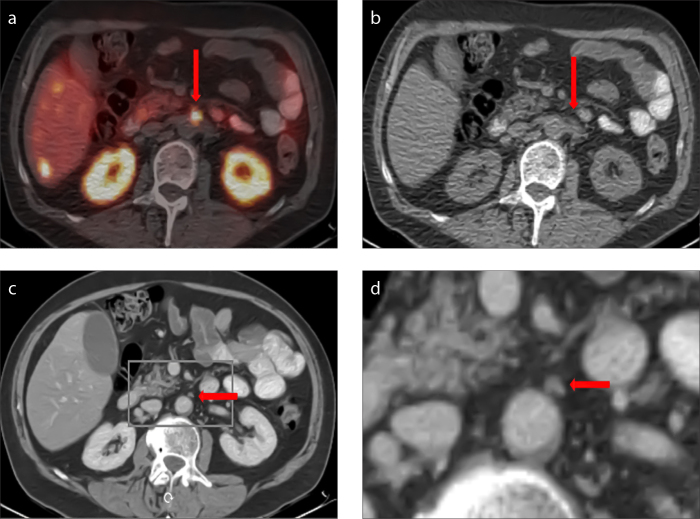

For the detection of lymphatic metastases, high-dose ceCT still seems to be necessary, despite the overall satisfactory performance of PET/ldCT. For diagnosing lymph node metastases, PET/ceCT is clearly superior (93% sensitivity and 86% specificity vs. 80% sensitivity and 65% specificity of PET/ldCT, Fig. 2).

Figure 2. a–d.

The cross-sectional 68Ga-DOTATATE PET/CT image (a) shows a focal tracer uptake (arrow); however, the use of cross-sectional low-dose CT alone does not permit the differentiation of unspecific intestinal activity versus lymph node metastasis (b, arrow). The additional use of contrast-enhanced CT (ceCT) provides a clear delineation of a lymph node as the source of the pathological tracer uptake (c, arrow), as seen in the magnified image section of ceCT (d).

When analyzing lymph node metastases, ldCT yields a high number of false-positive results (24) that cannot be proficiently excluded through PET. Differentiation between a lymph node metastasis and unspecific uptake in the small intestine can be difficult, leading to the high sensitivity and poor specificity of PET/ldCT in the detection of lymph node metastases. These false-positive results can be successfully excluded through high-dose ceCT.